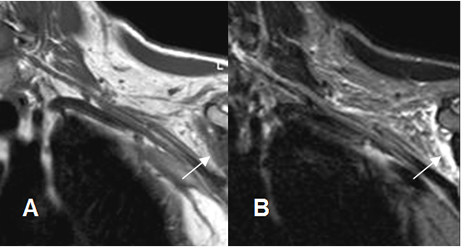

Fig 8. Neuropraxia.

A: RM coronal en T1y B: RM coronal en STIR. Cambios inflamatorios por encima de los vasos subclavios, que rodean las raíces nerviosas, las cuales permanecen integras. La lesión se produjo después de una luxación de hombro.